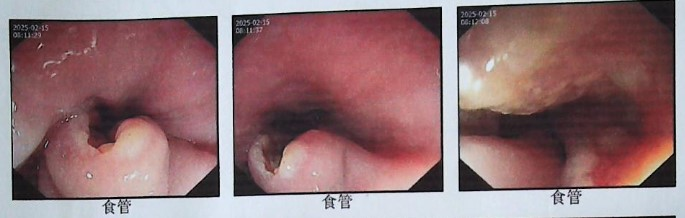

疗效评估:治疗6个周期后,患者复查PET/CT,提示肿瘤明显缩小。2025年7月8日,疗效评估达PR。

图片17.png图5 2025年7月8日PET/CT评效

2025年7月8日PET/CT对比2025年2月21日PET/CT:食管中上段病灶明显缩小,代谢降低,放射性摄取轻度增高(SUVmax2.5)。

图片18.png图6 治疗前(2025年2月21日,左)与治疗后(2025年7月8日,右)PET/CT